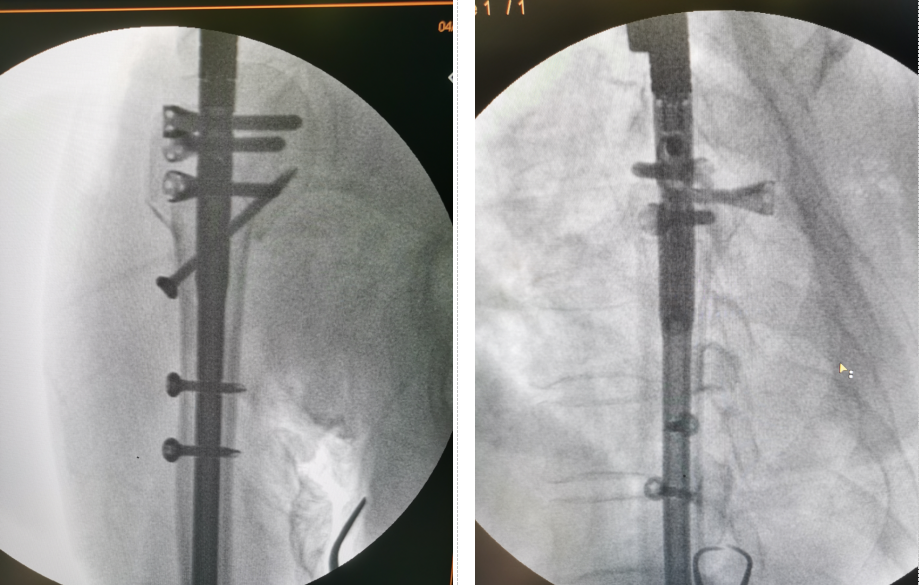

患者,女,73歲,因騎車時摔倒,左上肢著地導致左肱骨近端粉碎性骨折,收住我院骨創(chuàng)外科一病區(qū)。楊猛副主任接診后,給予患者詳細的查體,并完善術前檢查。左肩關節(jié)三維CT示患者為較為復雜的肱骨近端粉碎性骨折,骨折塊移位較大,分型為四部分骨折。出現(xiàn)該類骨折的患者往往骨質(zhì)疏松較為嚴重,骨質(zhì)量差,骨折粉碎較重,傳統(tǒng)切開復位接骨板固定為偏心性固定,容易出現(xiàn)內(nèi)固定松動,導致手術失敗,且切口大、剝離多、出血多。為讓患者以最小的創(chuàng)傷代價獲得最大程度的肩關節(jié)功能,經(jīng)團隊術前討論,決定為患者實施目前在國內(nèi)最先進的肱骨近端粉碎性骨折小切口復位肱骨多維髓內(nèi)釘(Multiloc)內(nèi)固定手術。

在制定了周密的手術計劃和康復計劃后,由楊猛副主任主刀,朱法豪主治醫(yī)師擔任助手,在麻醉科張顯平副主任醫(yī)師、手術室張建永護士長的共同配合下,應用手術室先進的X光全透視手術床,成功完成了手術。

該微創(chuàng)手術與傳統(tǒng)術式相比,手術時間短,出血少,創(chuàng)傷小,固定方式為多維平面鎖釘中心性固定,更為牢固,患者能夠早期進行肩關節(jié)功能鍛煉,因此能取得更為滿意的治療效果。